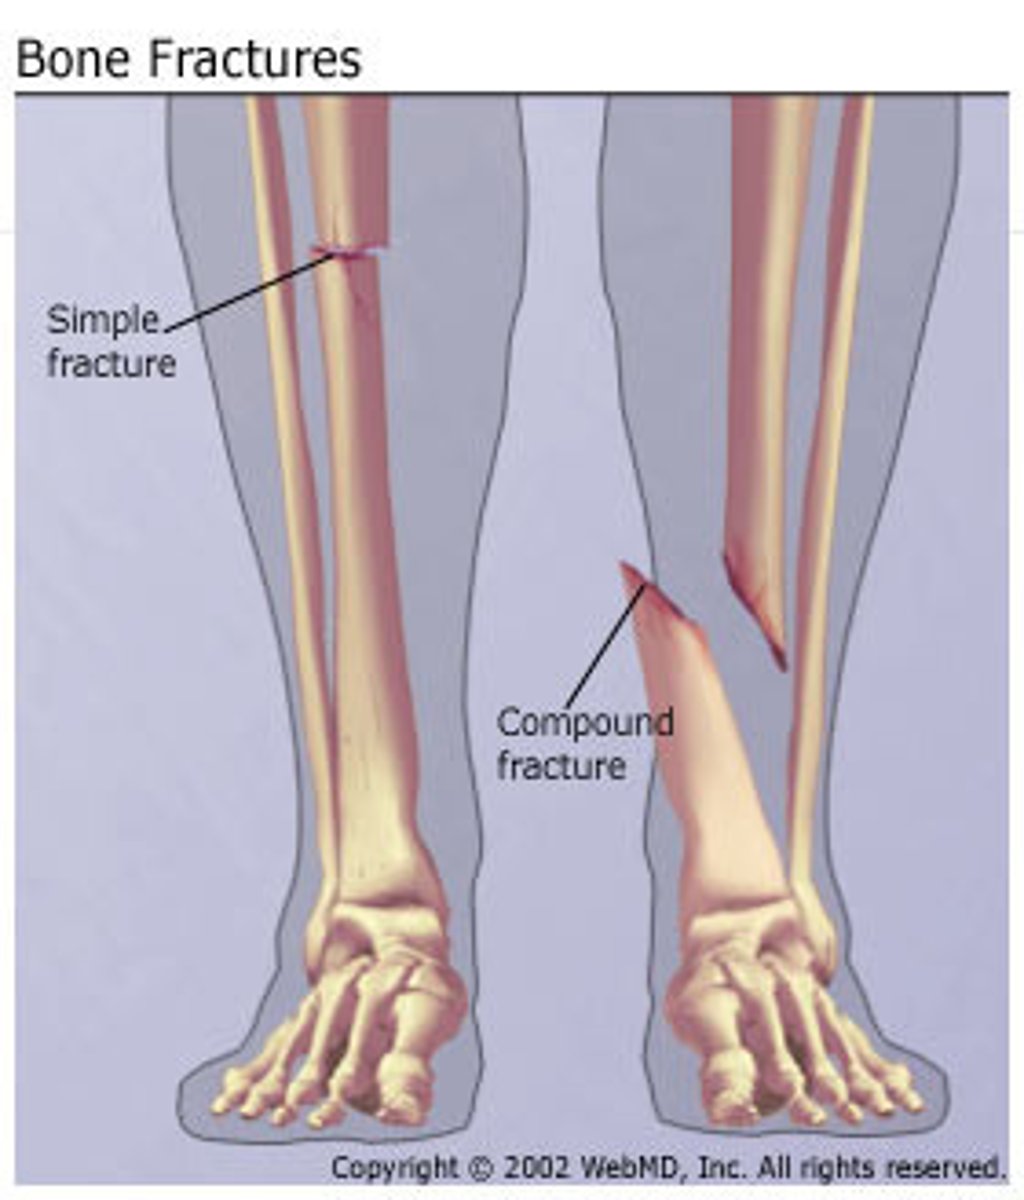

What is an open/compound fracture

- skin break

- fracture is piercing skin, exposing bone

What is a compression fracture

2 bones crushed together, collapse of vertebra

What is an impacted fracture

fracture fragments crushed together (broken bones are driven into each other)